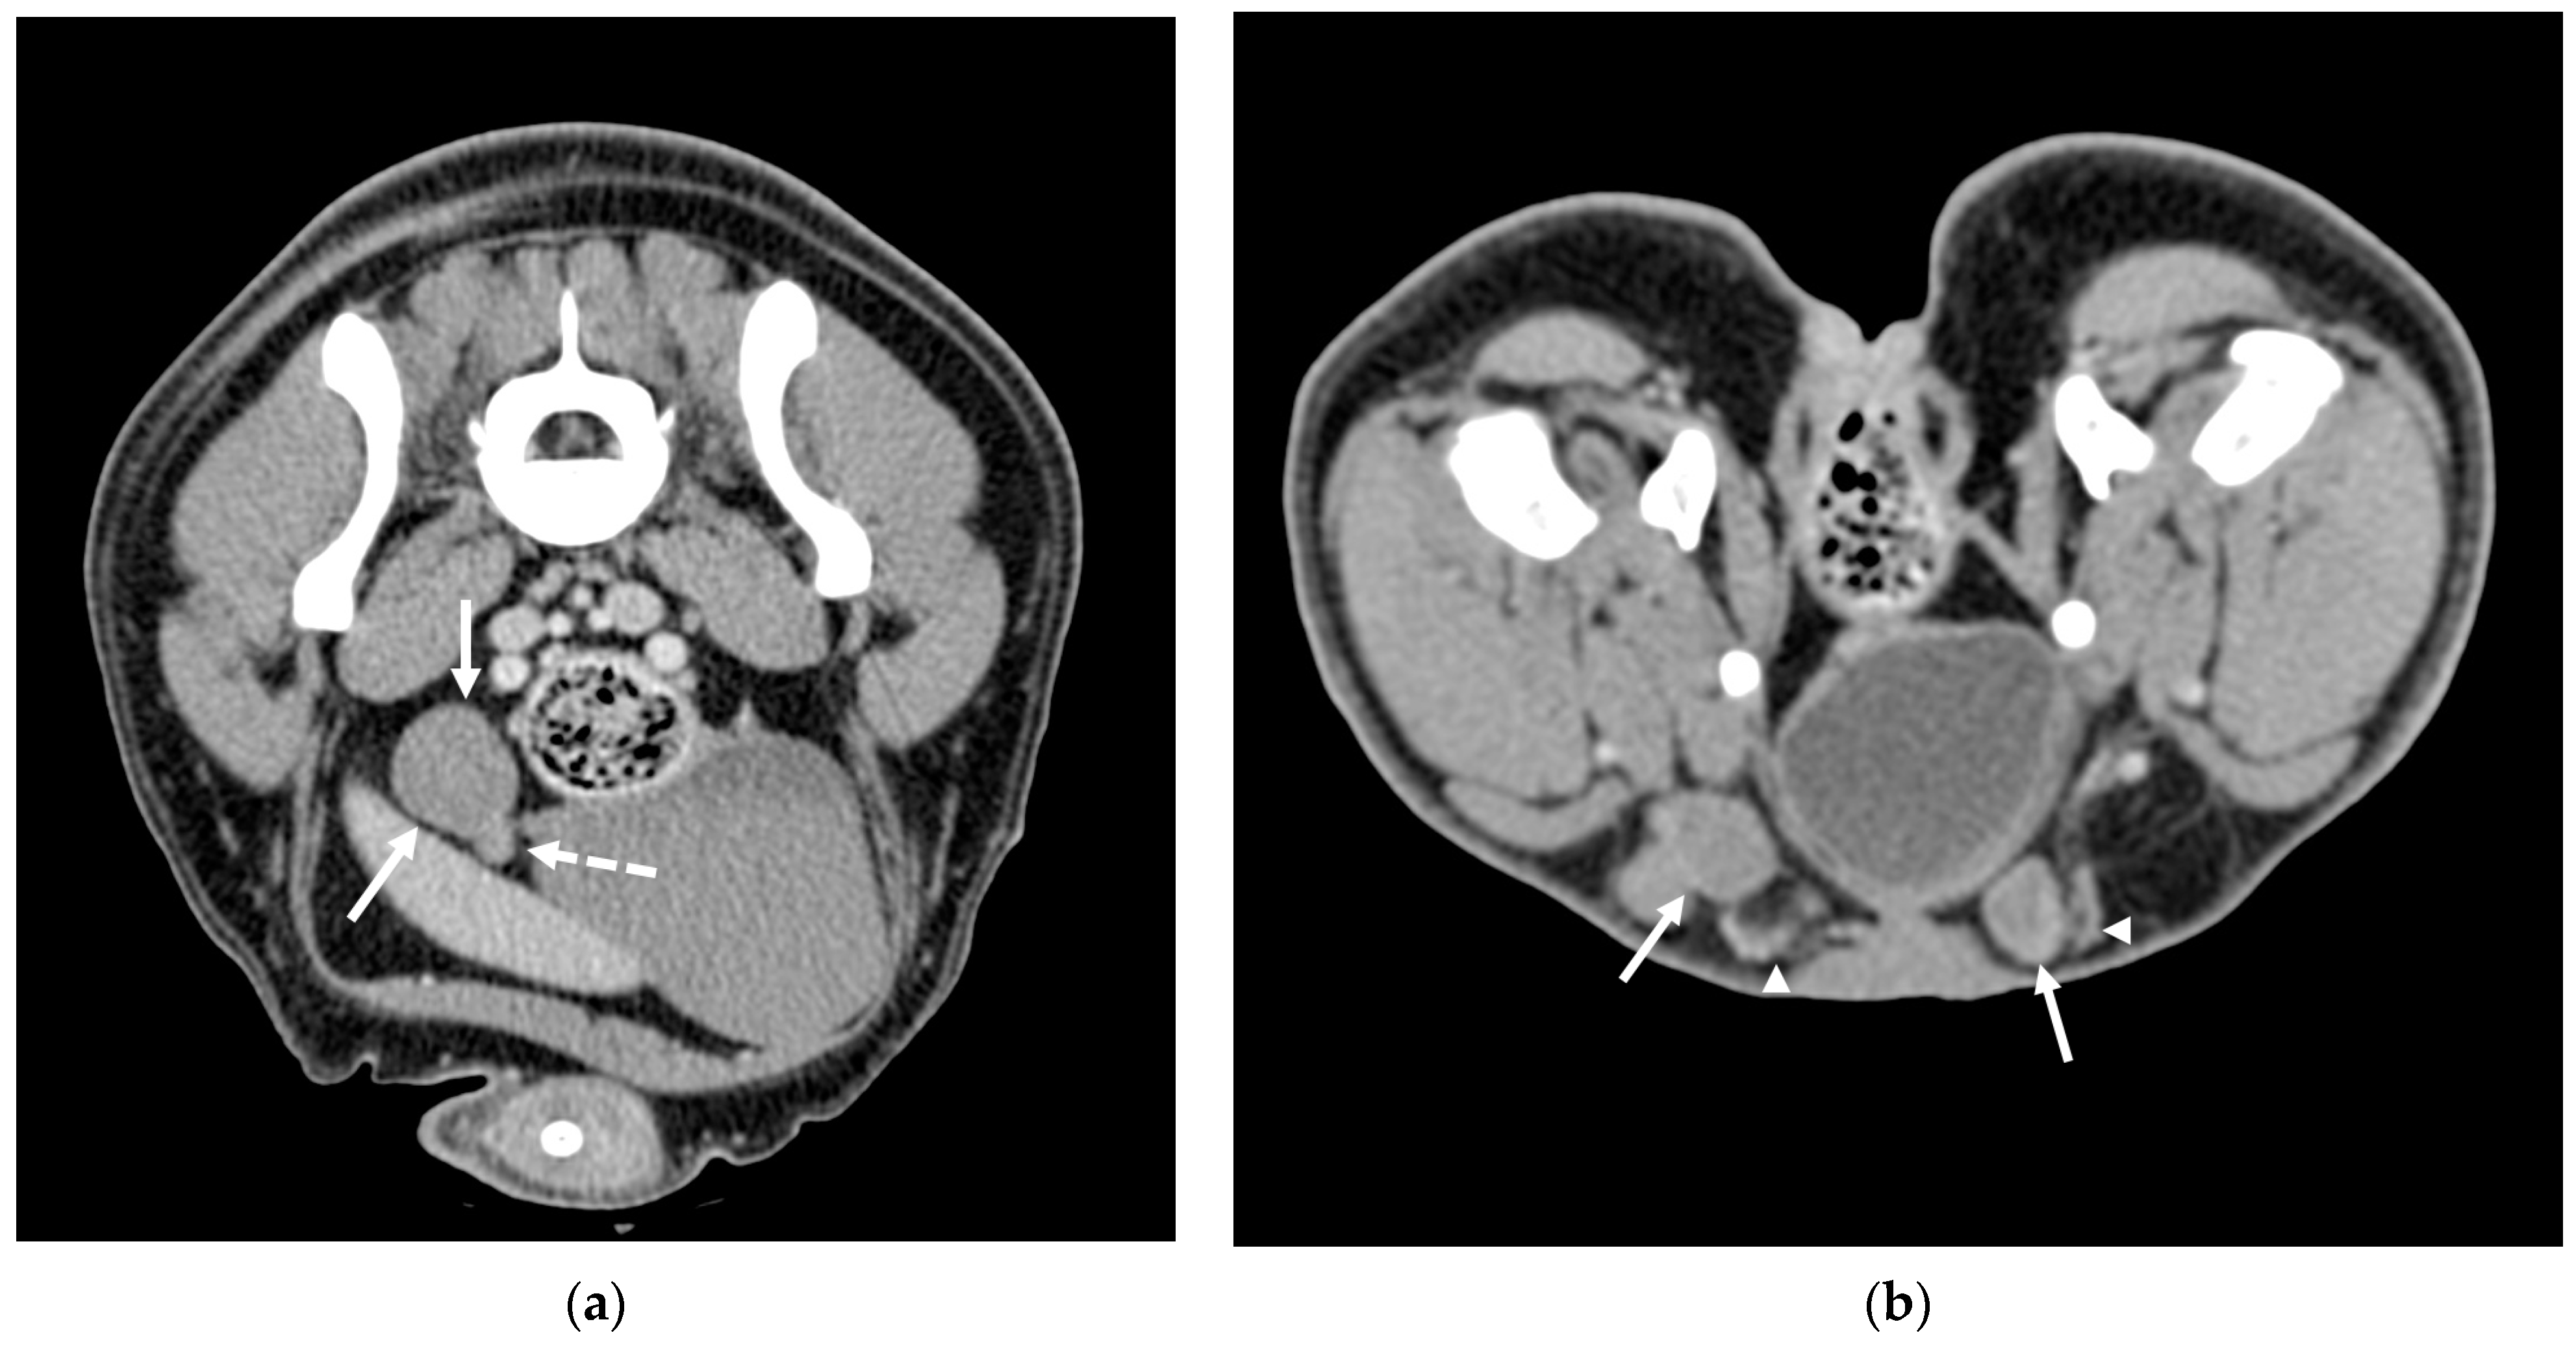

CT successfully identified all testicles, both abdominal and inguinal. The positions of the abdominal testicles varied significantly in relation to the median sagittal line; they were observed either deeply and centrally near the aorta and vena cava or superficially underneath the fascia (Figure 1). On transverse scans, their locations ranged between the sixth lumbar vertebra and the first sacral vertebra.

Figure 1. CT scans of two cases of cryptorchidism: (a) Post-contrast image showing an abdominally retained testicle (solid arrows), which appears homogeneously enhanced. The dashed arrow indicates the epididymis and pampiniform plexus, which show higher density compared to the testicular parenchyma. (b) Post-contrast scan of two inguinal testicles (solid arrows) with a visible pampiniform plexus (arrowheads).